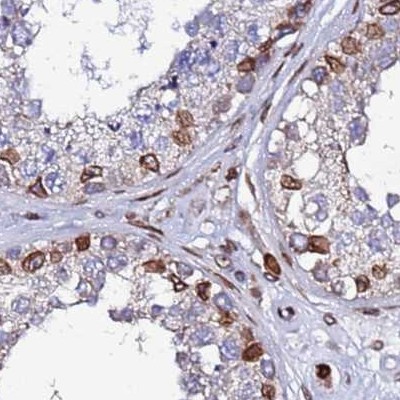

Immunohistochemical staining of human cerebral cortex, kidney, lymph node and testis using Anti-TOR1AIP1 antibody HPA047151 (A) shows similar protein distribution across tissues to independent antibody HPA050546 (B).